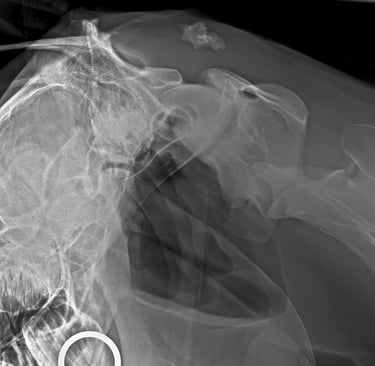

DIAGNOSTICO POR IMAGENES: ECOGRAFIA Y RADIOGRAFIA